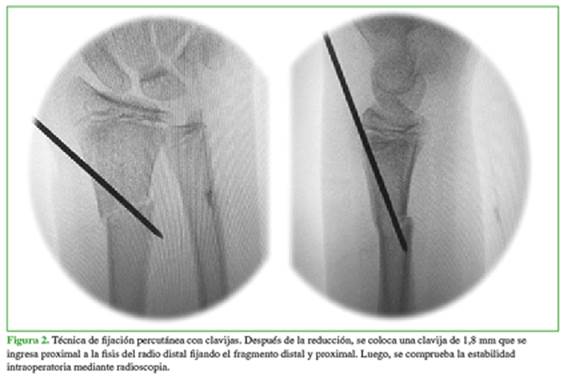

El procedimiento se realiza bajo anestesia general y monitoreo intraoperatorio. Se coloca al paciente en decúbito dorsal con el brazo abducido en la mesa de mano. Se procede a la asepsia y la antisepsia, y se colocan los campos según técnica. El arco en C ingresa paralelo al paciente desde distal y el monitor está frente al cirujano. Se realiza la reducción según técnica y se comprueba la estabilidad. Si, bajo radioscopia, no se logra una reducción satisfactoria o esta se considera muy inestable, se procede a la fijación. En los pacientes sometidos a FPC, se colocó una clavija de 1,8 mm que ingresa por debajo de la fisis radial de distal a proximal (Figura 2).